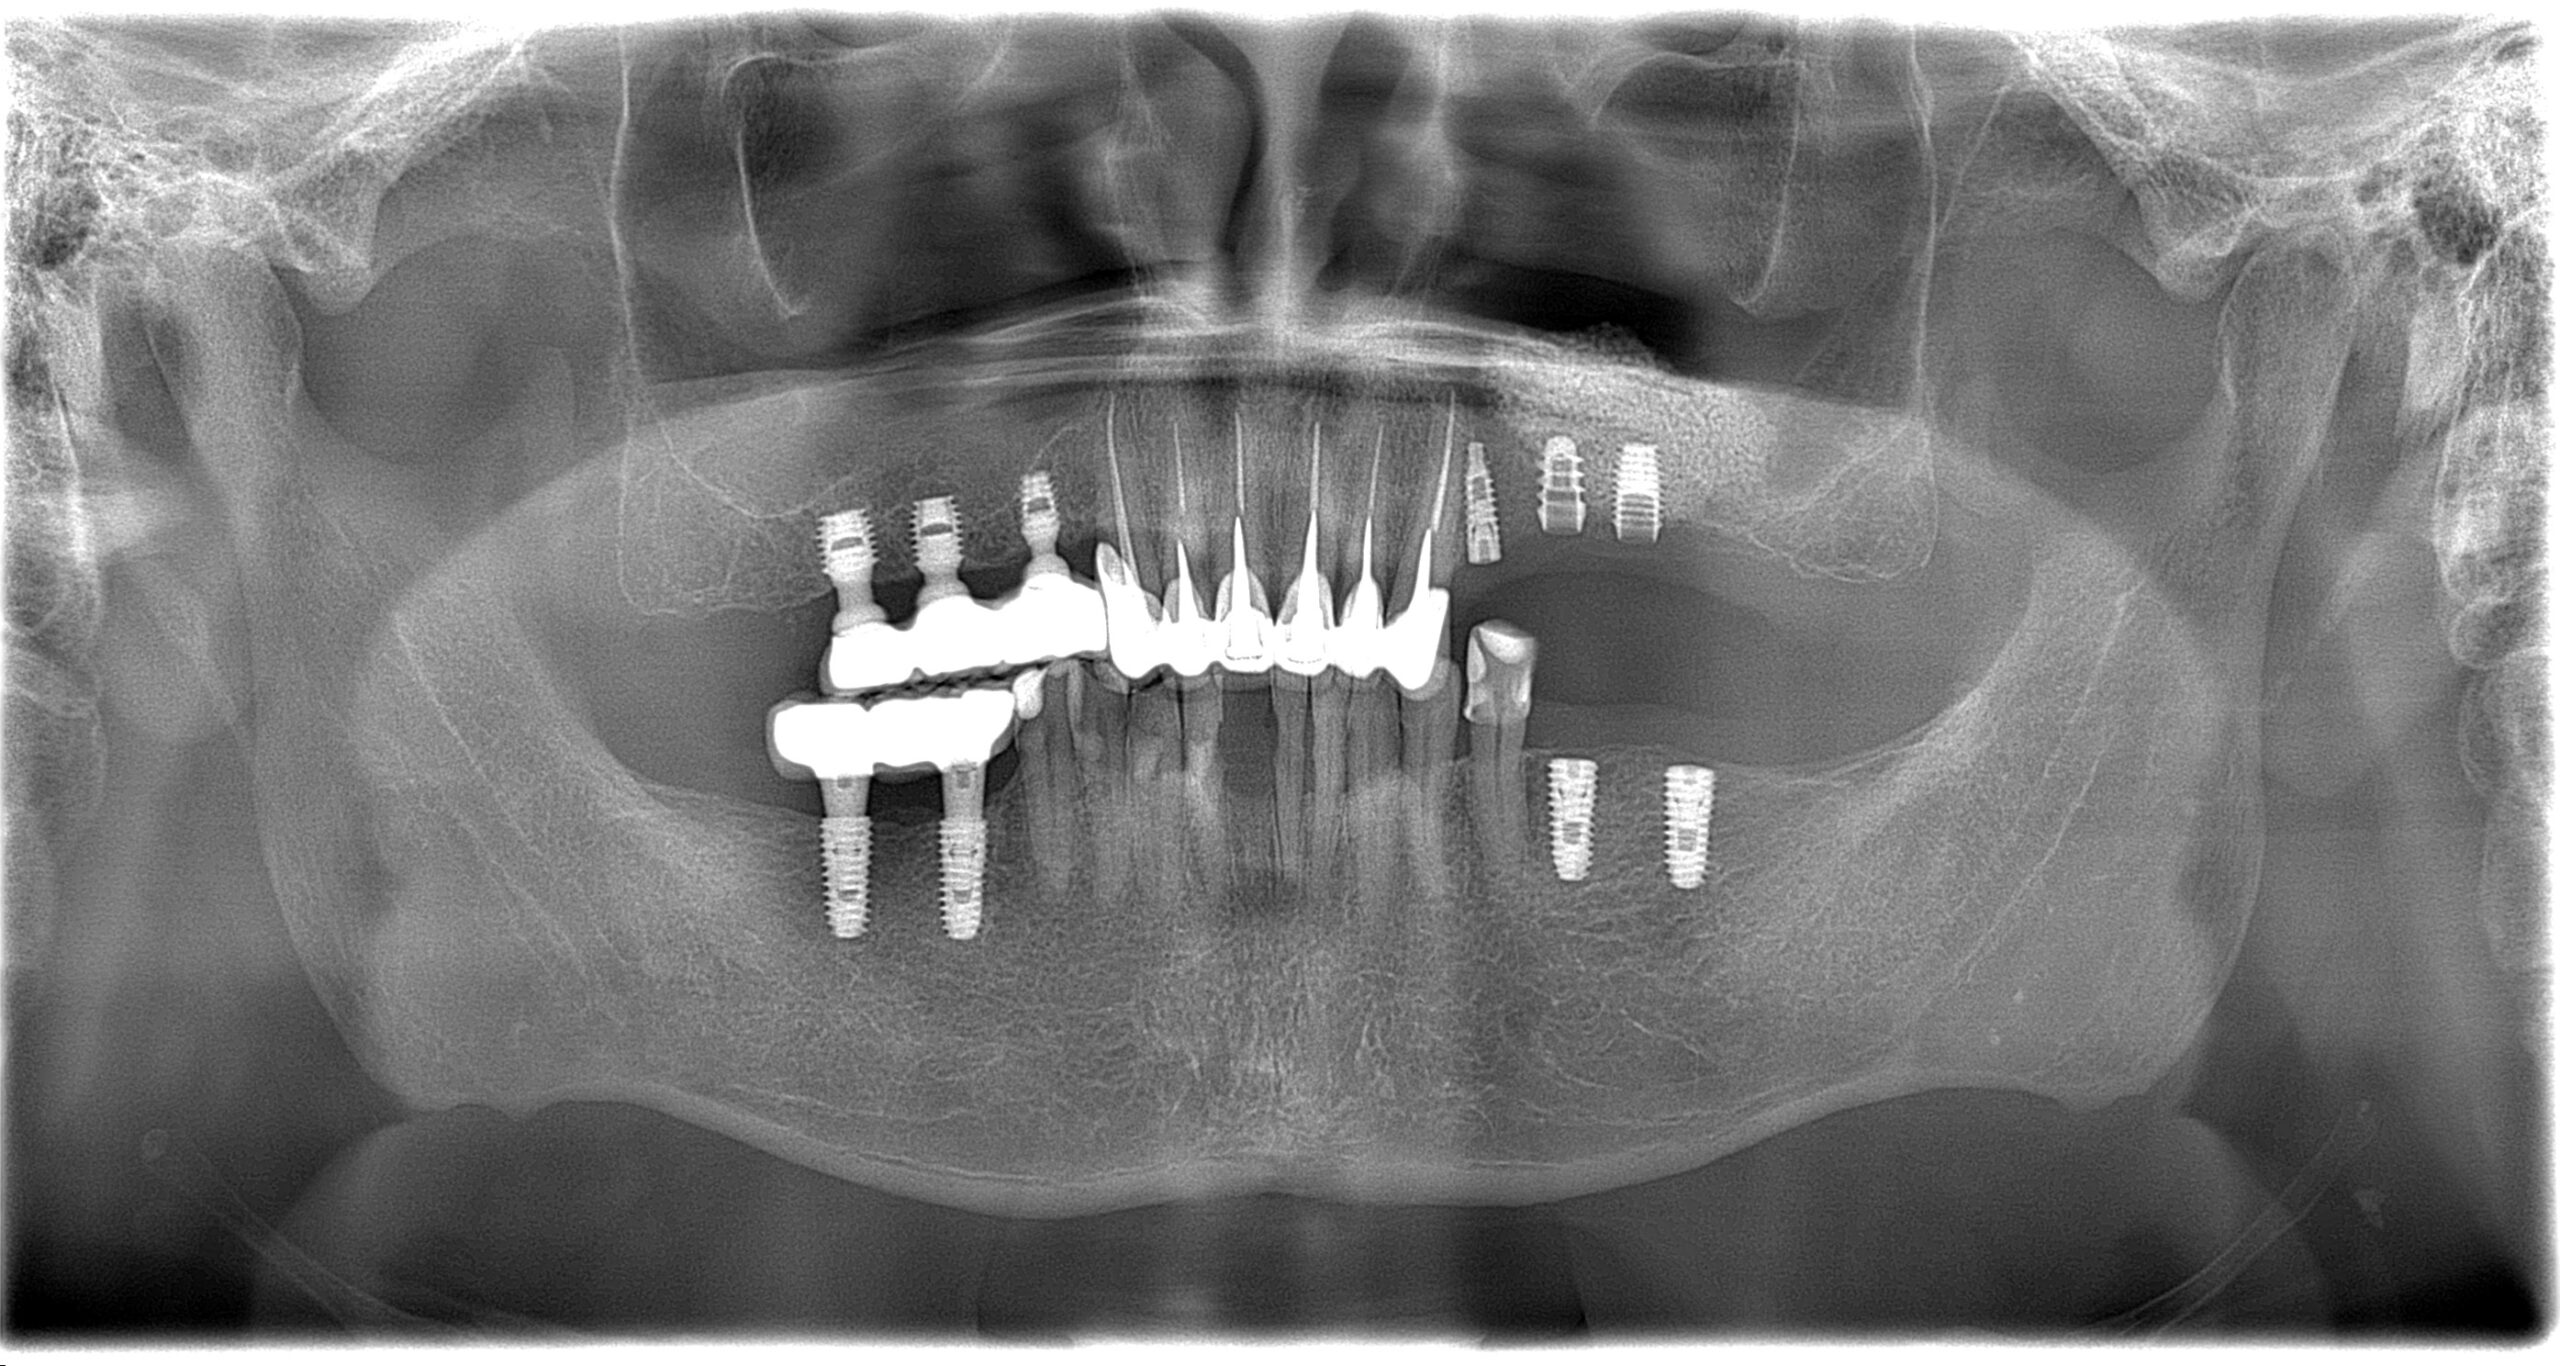

Імплантація